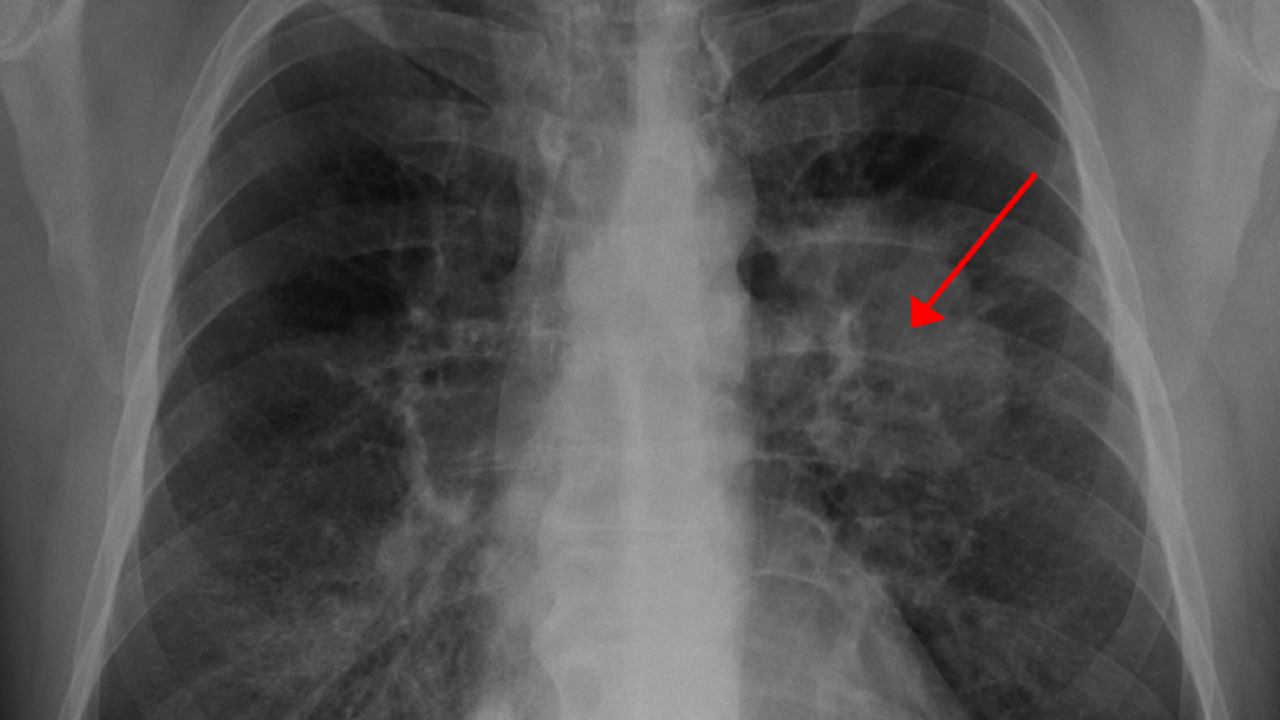

الأشعة التصويرية: وهي كثيرة ومنتشرة في جميع الدول، فيمكن أن نقوم بعمل تصوير رنين مغناطيسي من أجل التعرف على المرض، أو أيضًا التصوير الطبقي، كما أن هناك نوع آخر من أنواع التصوير يُمكن أن نكتشف منها مرض سرطان الرئة وهي المقطعي المحوسب.